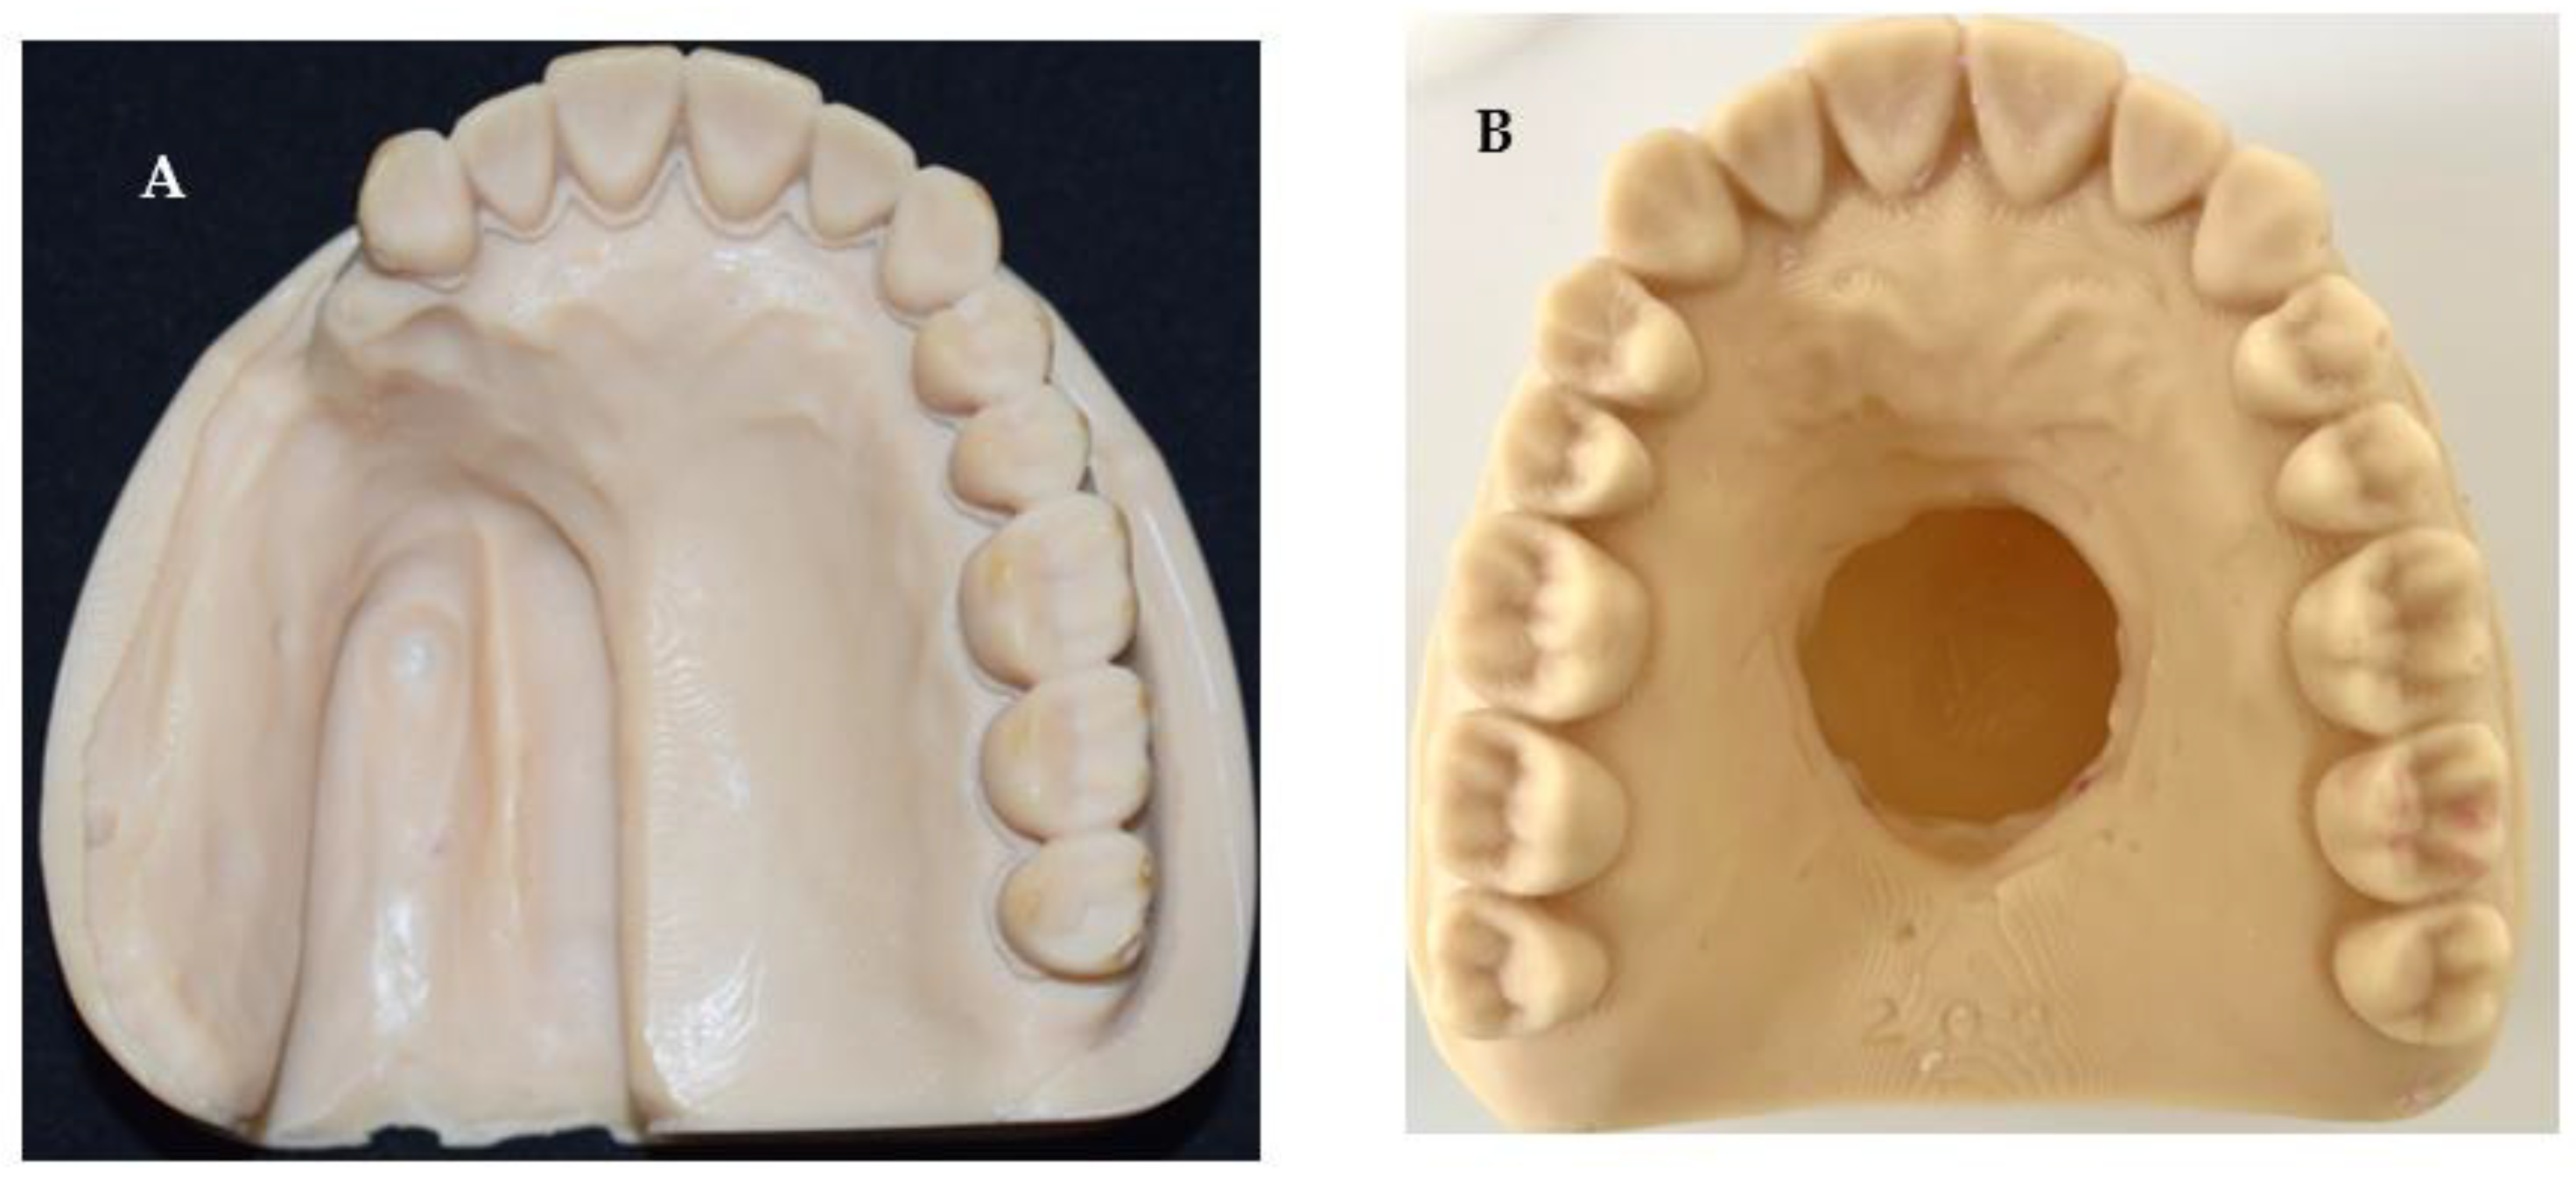

2.2.1. Conventional Impression Technique

2.2.2. Digital Technique

2.1. Defect Model Fabrication